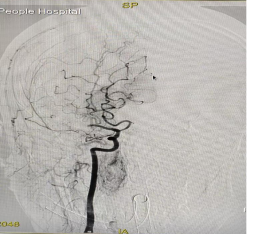

术前脑血管显影 术后脑血管显影

危急时刻,市人民医院立即开通“卒中中心”急性病救治绿色通道。启动开辟生命通道的多学科协作(MDT)机制,神经内科、神经外科、影像科等多学科专家紧急会诊。卒中医疗团队考虑到患者发病时间处于“黄金 6 小时”救治窗口内,在征得家属同意后,迅速制定了急性脑卒中急诊介入取栓治疗方案。随后,神经外科主任王晓明、神经内科副主任杜海兵、神经内科主治医师刘鑫华,麻醉科主治医师艾青慧、导管室护士长杨利等多学科医护人员同步响应紧急到位,在导管室通过微创介入方式直达血栓部位,成功抓取并取出堵塞血管的血栓,快速精准清除,重建脑部血供。整个手术历时仅50分钟,全程微创、出血少,术后造影显示,原本闭塞的大脑中动脉完全恢复血流,患者意识迅速清晰,肢体功能明显改善,言语功能也逐步恢复,手术效果立竿见影。